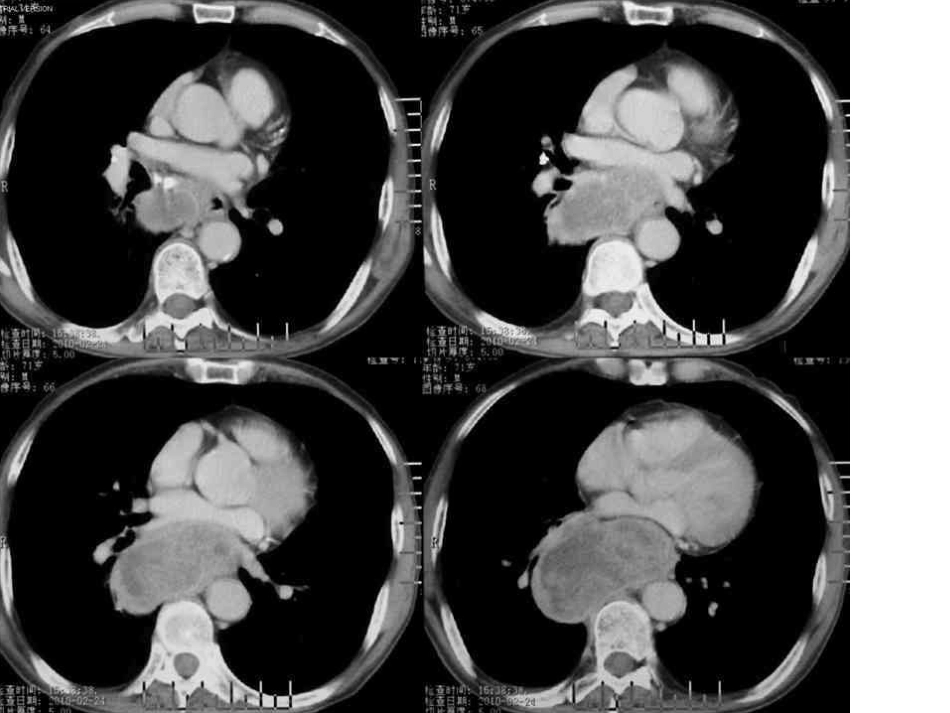

纵隔型肺癌•胃镜发现距门齿34~40cm食管右侧壁外压性改变,管腔外压约2/3,气管镜检查未见异常,以下是胸部增强CT如图:•纵隔型肺癌的分类纵隔型肺癌CT表现,通常可以分为3种类型:中央型、周围型及隐匿型。纵隔型肺癌的形成机制1)中央型肺癌合并肺不张,不张肺明显缩小紧贴纵隔,使纵隔增宽;2)靠近纵隔胸膜的周围型肺癌,似纵隔肿瘤;3)原发肺癌较小或位置隐匿,有纵隔淋巴结转移者纵隔增宽。尽管如此,纵隔型周围型肺癌在CT影像上还是不易和纵隔肿瘤鉴别。隐匿性肺癌CT可显示纵隔内广泛淋巴结融合成团块状,肺内可见小病灶或无病灶。三者在治疗及预后方面有所不同,因此正确诊断区分纵隔型肺癌的类型具有一定的临床意义。一般来说,纵隔型周围型肺癌恶性程度较高,病理上以未分化肺癌和小细胞肺癌多见,且为晚期。该病好发于上叶,主要侵犯前纵隔;其次为下叶。临床早期常有咳嗽咳痰、痰中带血、胸痛等症状,晚期出现上腔静脉综合征、进行性吞咽困难、霍纳综合征等症状。•纵隔型肺癌的CT表现1、纵隔中央型肺癌CT表现为:平扫肿块多为结节状,可有分叶,增强后呈不均匀强化;纵隔肺门肿大淋巴结平扫时密度均匀,边界尚光滑,增强后边缘强化明显;亦可见其他表现,如不张的肺叶紧贴于纵隔、病灶远端点片状阻塞性肺炎等。2、纵隔隐匿型肺癌CT表现为:纵隔广泛淋巴结融合成团块状,左下肺后纵隔旁见小结节状软组织影,增强后呈均匀强化。3、纵隔周围型肺癌CT表现为:平扫表现为贴近纵隔的肿块呈分叶状,有毛刺或棘状突起,增强后有均匀强化、外围强化及不均匀强化等;病灶内可有钙化,少数见支气管气相;受累支气管可表现为管壁增厚、管腔狭窄及阻塞;远端有阻塞性肺炎及肺不张。具体说来,纵隔周围型肺癌可有下属表现:•1)肿瘤直接征象:①肿块贴近纵隔并向纵隔侵犯,瘤体大部分位于纵隔,前纵膈最多见,后纵隔次之,中纵膈较为少见;②肿瘤分叶征较常见;③四分之一肿块内部可有中心性坏死,CT值约2~17HU;④肿瘤多为不均质强化,其强化幅度约20~40HU;⑤较少病灶内可见砂粒样钙化,钙化灶CT值可达105~157HU。2)瘤肺界面:大多数病例肿块与肺组织界面非常毛糙,局部肺纹理可伸入肿块;约四分之一病例在肺窗上肿块边缘可见毛刺或棘状突起。这是因为肿瘤起源于肺组织,在瘤肺界面仍有周围型肺癌的特点,如毛刺、棘突影以及一些增粗肺纹理影。这是纵隔型周围型肺癌重要CT征象。有文献报道纵隔胸膜下周围型肺癌肿块边缘与纵隔胸膜呈锐角相交,但是肿块与纵隔胸膜呈钝角者更为常见,主要因为肿瘤体积较大,瘤体与胸膜接触面较大,因此该征象对诊断直径>3cm的纵隔胸膜下周围型肺癌价值不大;而瘤体<3cm的肺癌还是有一定的鉴别价值。3)病灶与纵隔大血管的关系:纵隔血管表现为受压移位,以上腔静脉受压最为常见,上腔静脉变扁或消失不显影,临床上出现上腔静脉综合征。⑷远处转移:纵隔型周围型肺癌病情多已是晚期,因此常见远处转移,其中以淋巴结转移最为常见,其次为胸膜转移。•纵隔型周围型肺癌鉴别诊断1)恶性胸腺瘤:一般多见于青少年;肿瘤呈浸润性生长,但与肺组织交界面仍较清晰,肿块边缘无明显毛刺影,侵袭性胸腺瘤容易出现囊变和钙化,其瘤体内囊变影与纵隔型肺癌内坏死有所不同,前者可见囊壁影比较均匀,而后者是以中心性坏死为主,周围实质性成分较多,且厚薄不均;侵袭性胸腺瘤引起胸水和心包积液较纵隔型肺癌多见;纵隔大血管以受压后移为主。2)恶性淋巴瘤:以青少年多见,临床无明显咳嗽、咳血,与肺组织分界光整,肿瘤呈多发结节或融合肿块样,前者不易与纵隔型周围型肺癌混淆,后者有时呈单一肿块与纵隔型周围型肺癌非常相似,但恶性淋巴瘤以包埋纵隔血管浸润性生长为主,血管受压移位变形改变(尤以上腔静脉)不及纵隔型周围型肺癌明显。从病变部位看,恶性淋巴瘤常累及气管旁、主肺动脉窗、隆突下及右肺门淋巴结,而纵隔型肺癌以侵犯前、后纵隔多见。•3)纵隔转移性淋巴结肿大:常多发,多位于中纵隔,在CT增强图像上,多数转移性淋巴结增大呈均匀密度强化,少数伴淋巴结中心液化坏死。单发肿瘤>3cm时较难与纵隔胸膜下周围型肺癌鉴别,但肿块与肺...